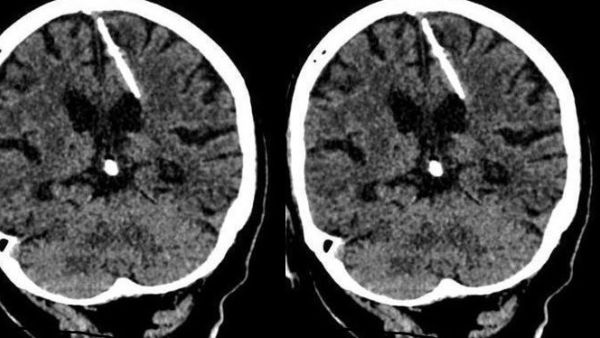

اكتشف اطباء روس بالصدفة ابرة طولها ثلاثة سنتمترات موجودة منذ ثمانين عاما داخل دماغ امرأة مسنة اثناء قيامهم باجراء فحص لها بالتصوير المقطعي.

وأضافت أن الفحوص اظهرت ان المراة تعيش مع الابرة البالغ طولها ثلاثة سنتمترات داخل دماغها "منذ ولادتها" ما يؤكد ان والديها كانا قررا التخلص منها، لكن محاولتهما لم تفلح.

واوضحت الادارة ان الفحص اظهر ان الابرة اخترقت الفص الجداري الأيسر لدماغ المراة، لكنها كتبت لها النجاة حيث لم يتسبب ذلك في وفاتها كما كان يأمل والداها.